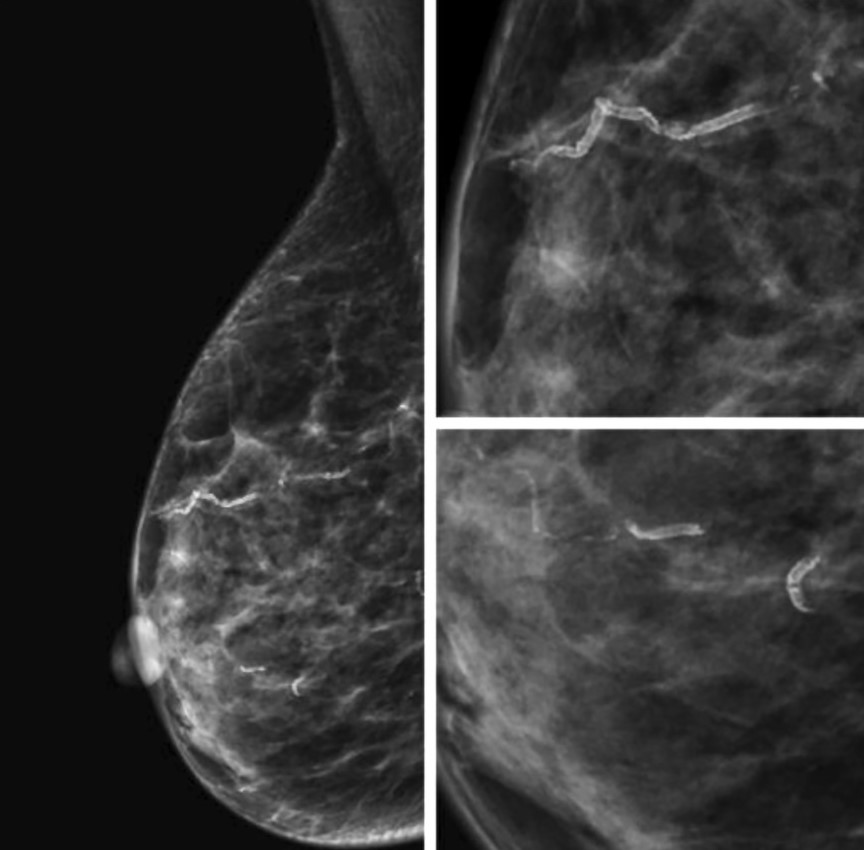

Сосудистые кальцинаты определяются на маммограммах как параллельные гиперденсные линии по ходу стенок сосудов. Их также называют кальцинатами Мёнкеберга, они поражают среднюю оболочку сосуда [13, 14] (Рис.2).